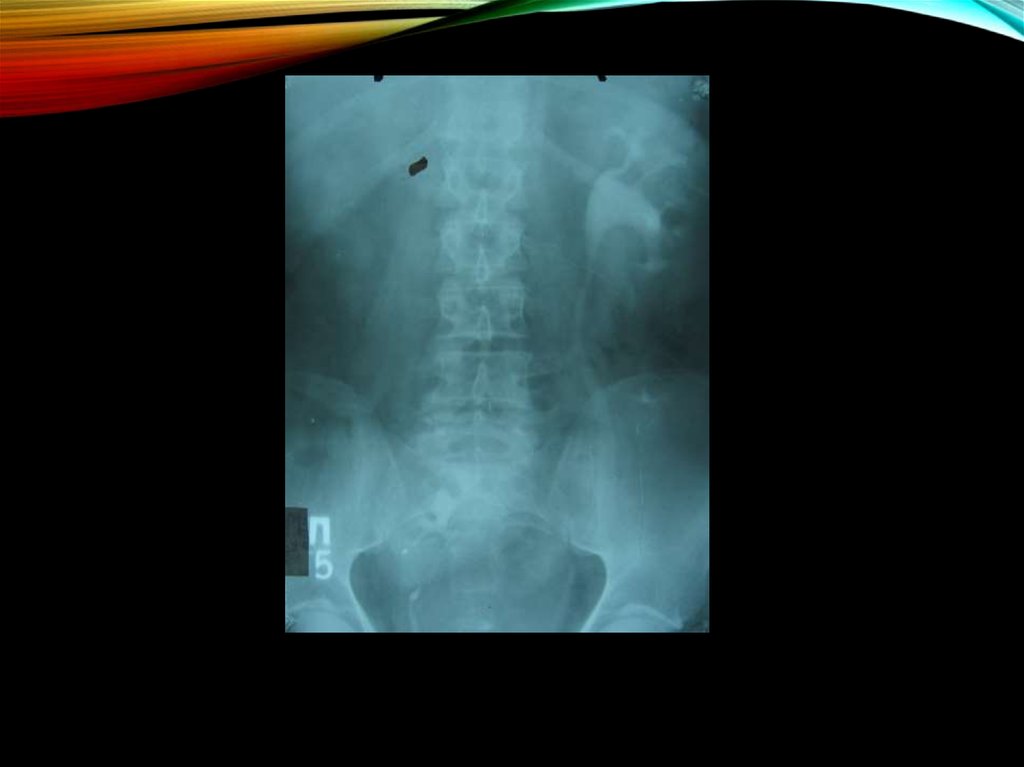

14. Изменения рентгенологической картины:

ИЗМЕНЕНИЯ

РЕНТГЕНОЛОГИЧЕСКОЙ

• увеличение в объеме пораженной почки

КАРТИНЫ:

• не контрастируются мочевыводящие пути на

пораженной стороне

• отсутствует контур поясничной мышцы

• при ретроградной пиелографии - сдавление чашечки и

лоханки, ампутация одной или нескольких чашечек